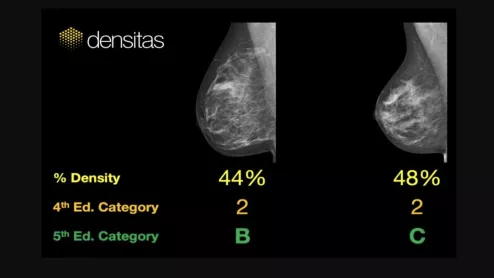

An example of commercially available artificial intelligence (AI) automated grading of breast density on mammograms from the vendor Densitas..

Connie Lehman, MD, chief of breast imaging, co-director of the Avon Comprehensive Breast Evaluation Center at Massachusetts General Hospital, discusses how artificial intelligence (AI) is being implemented in breast imaging.